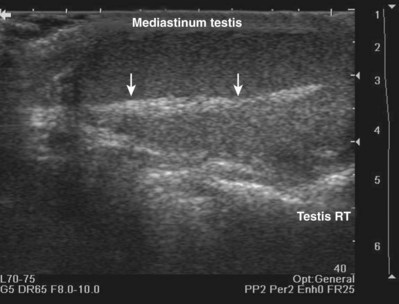

When interacting sound waves are in phase or out of phase, their amplitude will be enhanced or diminished. This pattern of interference is partially responsible for the echo architecture or texture of organs. One pattern of interference, commonly called “speckling” (Fig. 4–19), is seen in organs with fine, internal histology such as the testis.

Figure 4–19 Fine internal echogenicity called “speckle” is caused by scattering of sound waves and the resultant pattern of interference. Note the resulting finely granular, homogenous echogenicity (arrows) of the testicular parenchyma.